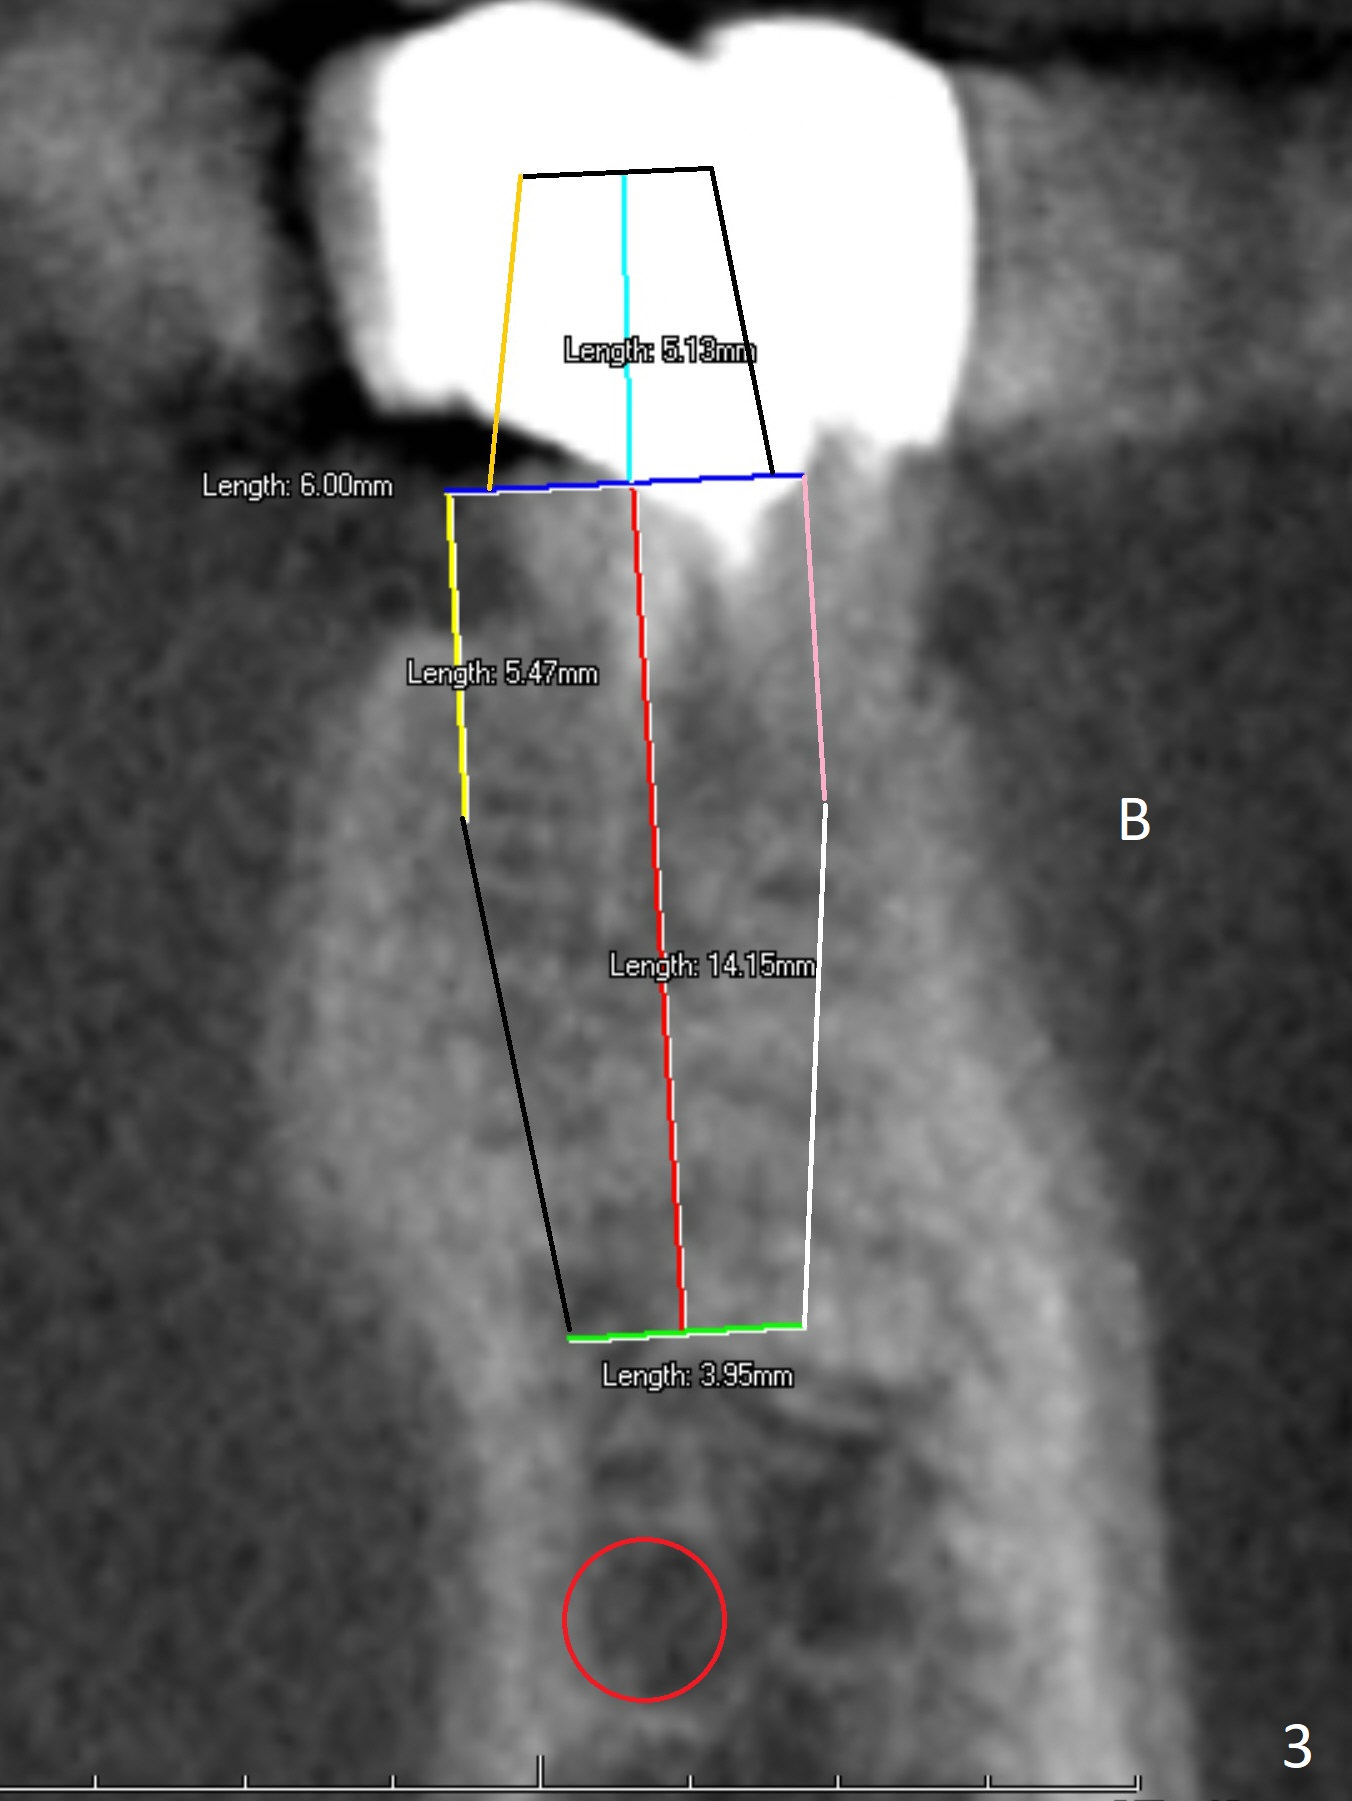

A 64-year-old man feels that the lower right 1st molar irritates the tongue. The mesial root fragment is sharp lingually (Fig.1). Initial osteotomy depth is 14 mm (gingival margin, Fig.2), as lingual as possible (Fig.3 CT taken on 01/21/2011).